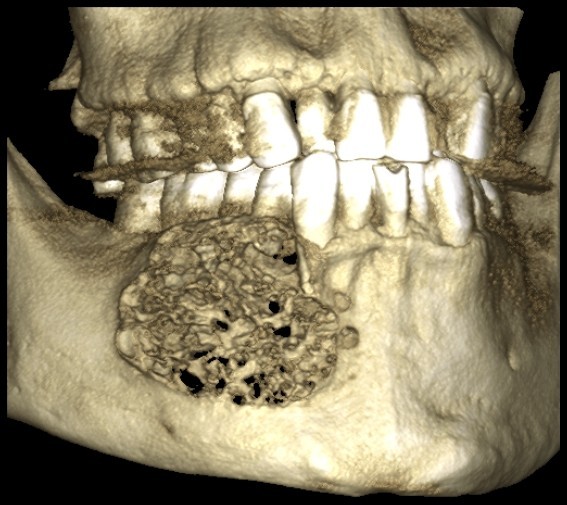

常规开展:数字化根尖片/横断牙合片、数字化口腔曲面体层片、头影测量侧位/正位片、手腕骨片、颅颌面CBCT、牙齿CBCT的检查以及涎腺造影、窦道 瘘管造影。

颅颌面CBCT

诊断范围涉及牙体牙髓病、牙周病、阻生牙/多生牙定位、种植牙术前CT评估分析、颞下颌关节CT诊断分析、,颌骨及涎腺疾病、颌面发育畸形、正畸治疗辅助诊断等大部分颌面部疾病,为临床医疗提供强有力的支持。